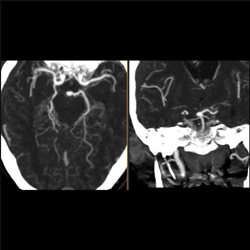

Aneurysm 02

76 yo female who had a syncopal episode and fell striking her head; now has reduced level of consciousness. There is a history of advanced cardiovascular disease. CT, CTA